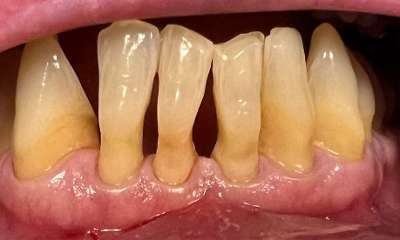

Bioclear composite treatment to get rid of "black triangles" and spaces between lower front teeth. These spaces are common on teeth that have had gum recession and roots exposed.